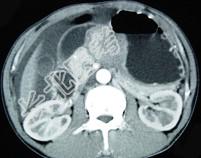

- 单项选择题男,65岁, 中上腹痛腹胀、消瘦、乏力、纳差,影像检查如图, 最可能的诊断是  (    )

- A、胃间质瘤

- B、萎缩性胃炎

- C、肥厚性胃炎

- D、胃窦癌

- E、胃淋巴瘤